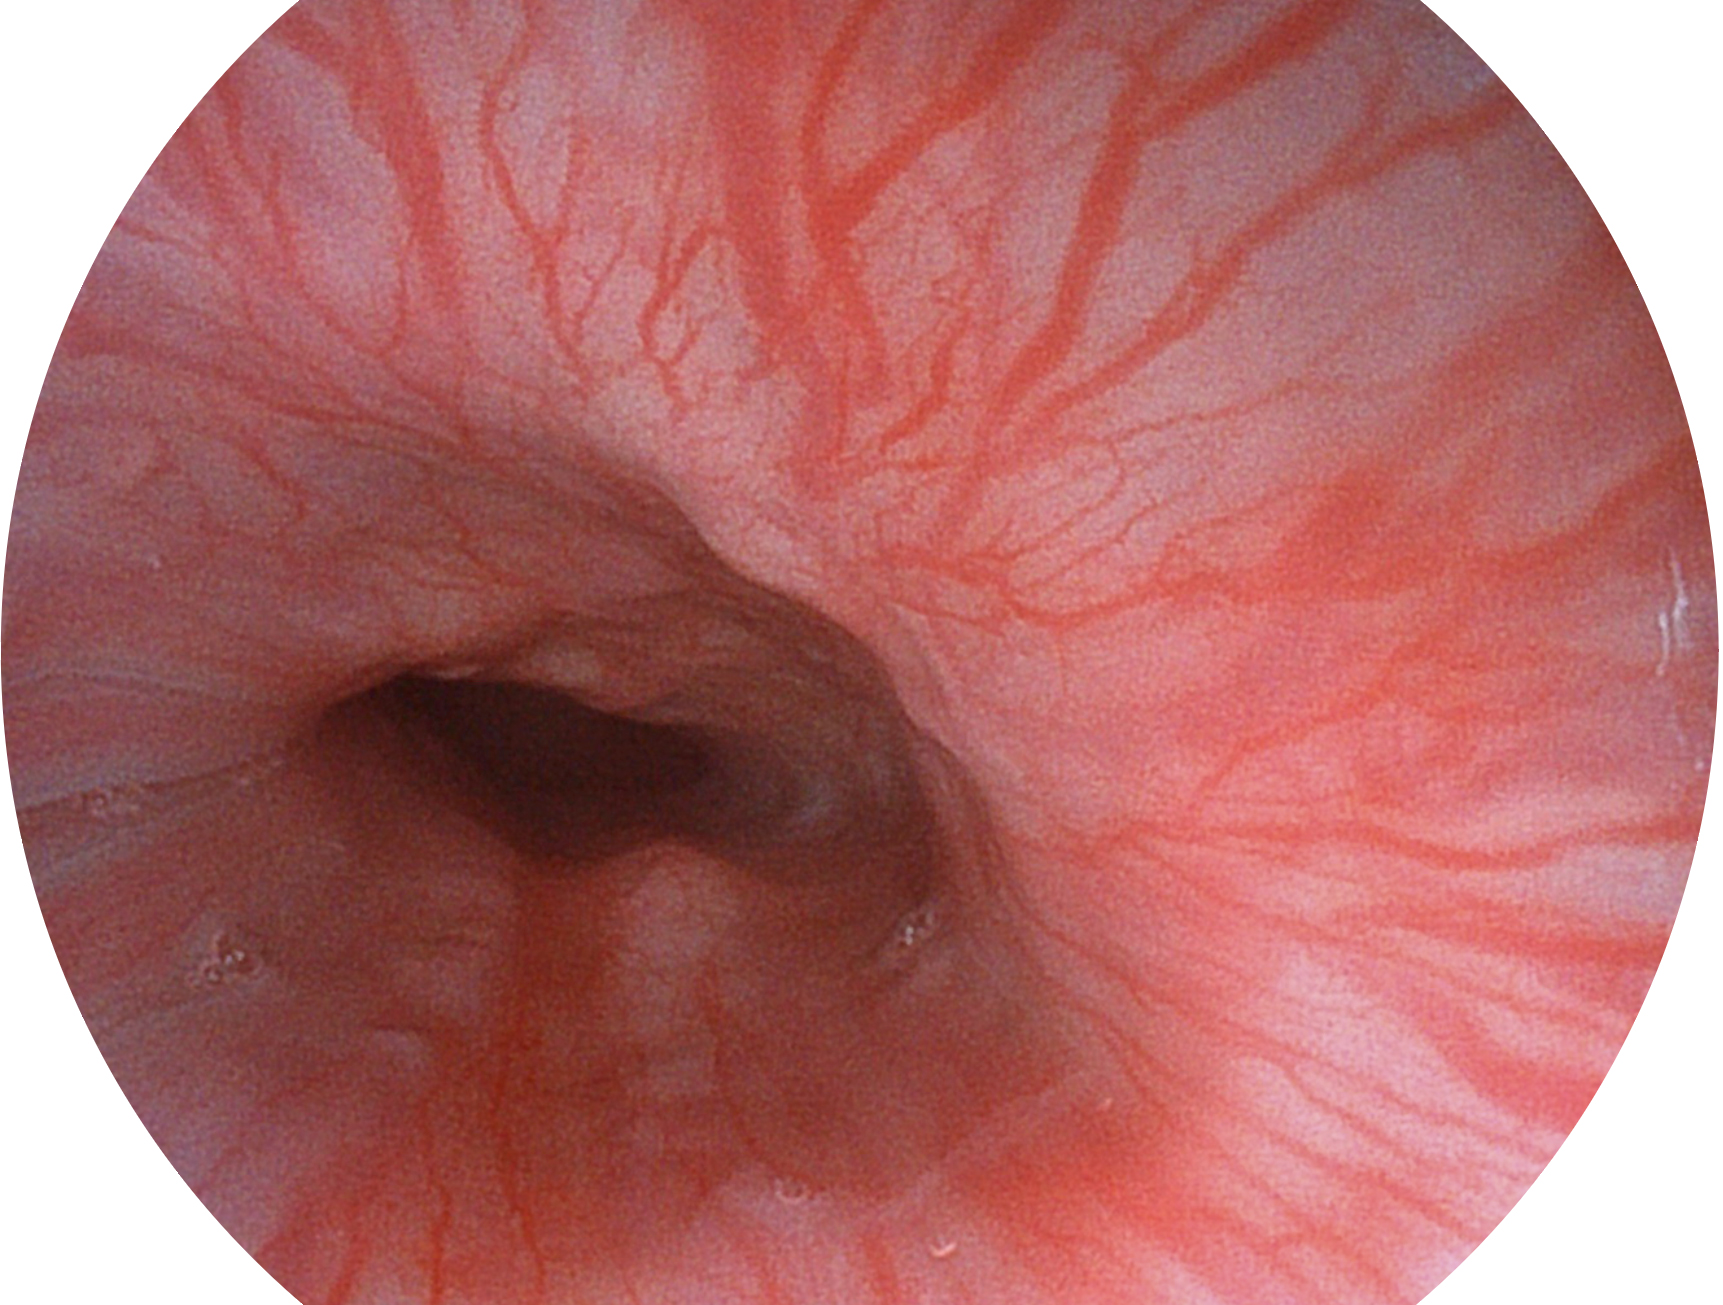

milan米兰新开发的内镜染色技术,主要是基于多波长LED 光源的开发,VLS-55Q 四波长LED 光源是由四个不同颜色的LED光按照相应照明模式所规定的特定发光比例进行合束后形成,合束后形成的照明光的光谱由红光、绿光、蓝光及蓝紫光这四个不同的波段范围构成。具有更高光谱自由度,通过光谱比例的控制,实现了聚谱成像技术,英文全称为“Spectral Focused Imaging, SFI”,缩写为“SFI”和光电复合染色成像技术,英文全称为“Versatile Intelligent Staining Technology, VIST”,缩写为“VIST”。